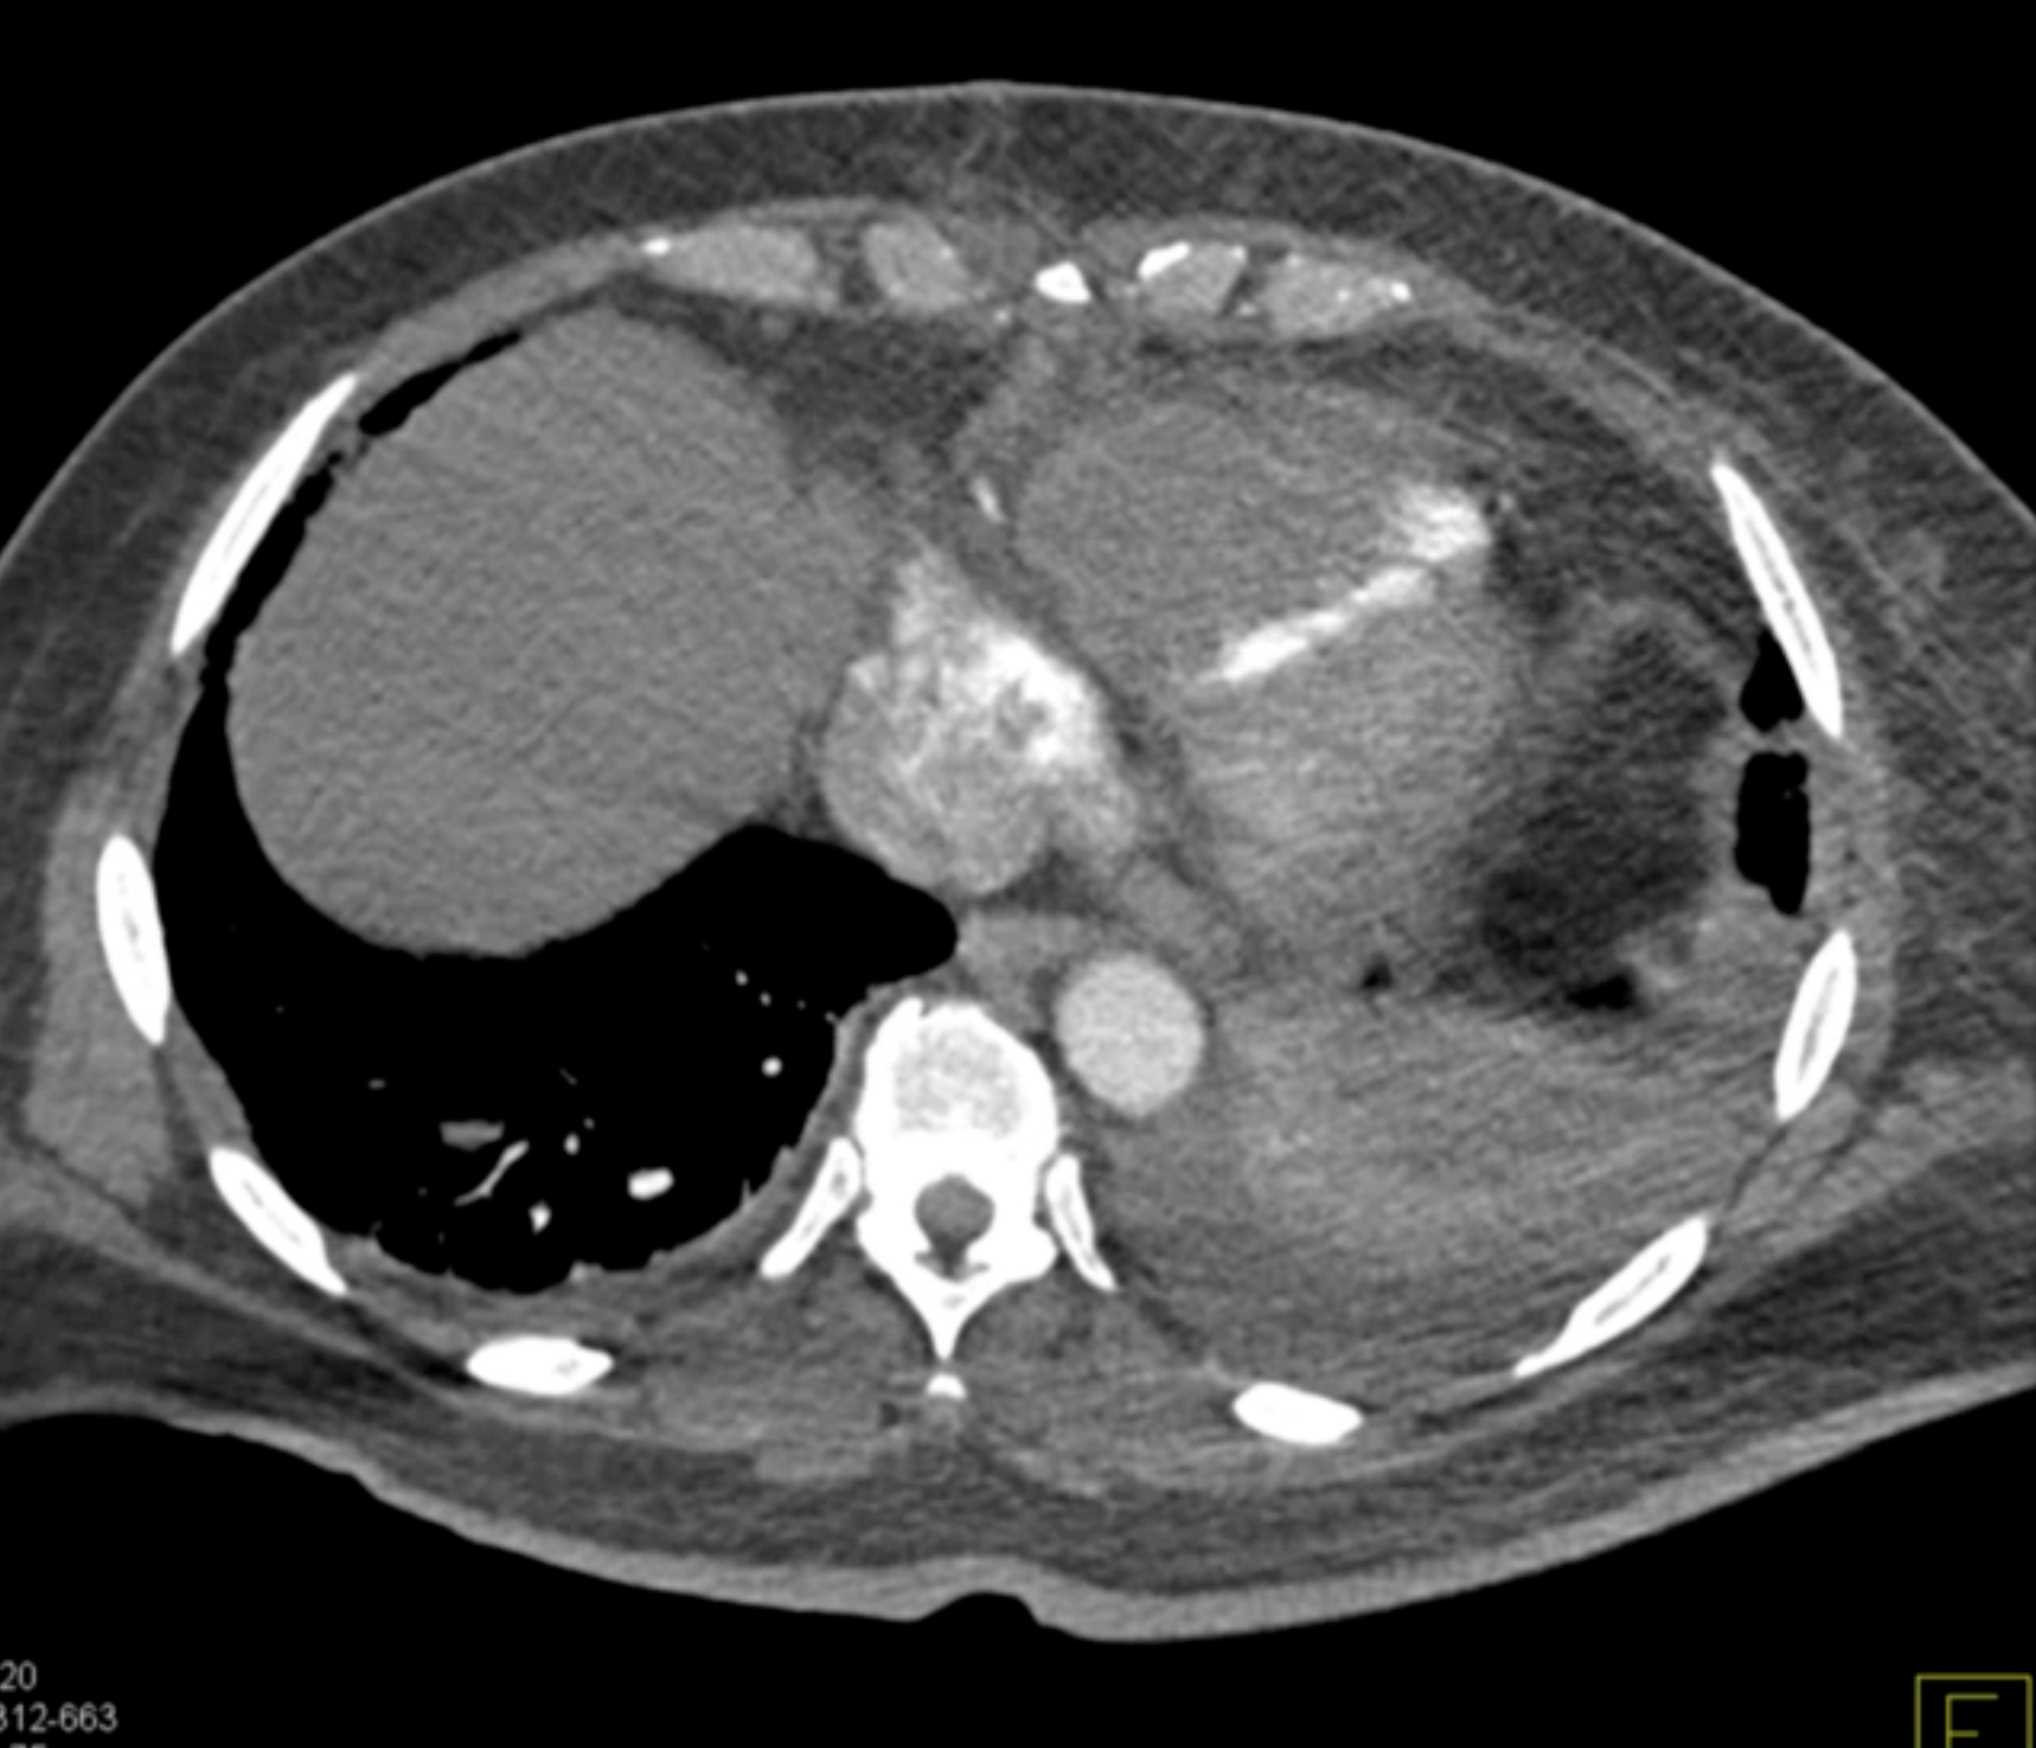

Primary Spindle Cell Carcinoma of the Right Ventricle